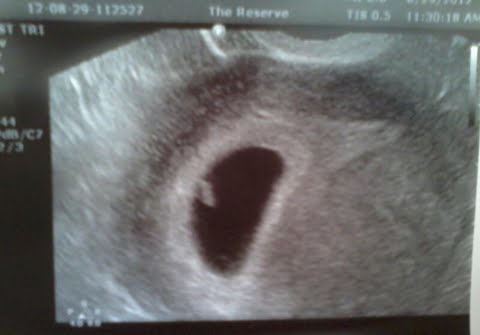

Ramzi theory guesses?

I wish I had never read anything about the Ramzi theory!!! I need to have my internet privledges taken away! I had my scan today at 5w6d, it was a vaginal scan so from what I understand (which isnt much) this is a true image, and the tech did confirm that much but wouldnt say anything else. I later found out I have a large cyst on my left ovary so I think that is why she wasnt saying much. Anyway, does this mean girl or boy?

Attachment 4313

I don't think you can tell which side of the uterus that implantation has taken place in this pic...but maybe someone else will have some insight. GL!

,i think its girl cuz its on left side acording to ramzi left side means girl right side means boy/.its guess only ok